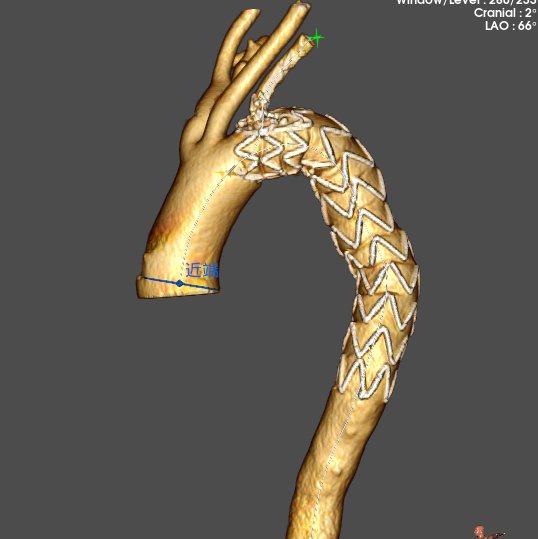

Cratos™ thoracic branch stent graft system is indicated for the treatment of thoracic aortic dissection involving aortic arch pathologies, enabling simultaneous endovascular repair of the aorta and reconstruction of supra-aortic branch arteries.

Cratos™ thoracic branch stent graft system is indicated for the treatment of thoracic aortic dissection involving aortic arch pathologies, enabling simultaneous endovascular repair of the aorta and reconstruction of supra-aortic branch arteries.